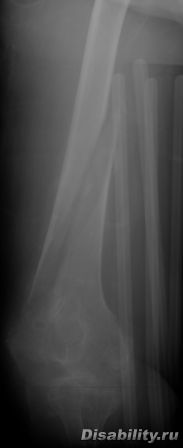

Здравствуйте,Доктор! 15 лет назад,через год после травмы позвоночника я вывихнул голеностоп(когда стоял в вертикализаторе).

Так получилось,что сустав не вправили,а лишь сняли отек.

Имеет ли смысл сейчас делать операцию на голеностопе,т.к. только эта травма мешает мне ходить(от бедра,на костылях).Как Вы считаете?

Консультирую по вопросам травмы и хирургииЗдравствуйте,Доктор! 15 лет назад,через год после травмы позвоночника я вывихнул голеностоп(когда стоял в вертикализаторе).

Если вопрос ещё актуален, то для ходьбы вывих должен быть устранен, нужна операция.извините за запоздалые ответ, не увидел ваш вопрос.

Консультирую по вопросам травмы и хирургииЕсли вопрос ещё актуален, то для ходьбы вывих должен быть устранен, нужна операция.извините за запоздалые ответ, не увидел ваш вопрос.